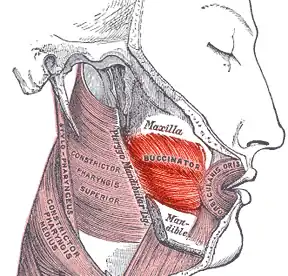

Bucinator muscle

| Bucinator muscle | |

Bucinator outlined in red. | |

Position of buccinator muscle (red)

Position of buccinator muscle (red) -